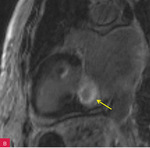

Rycina 8A, B. Obrazy rezonansu magnetycznego w projekcji pięciojamowej (A) i dwujamowej (B) z późnym wzmocnieniem kontrastowym – widoczna zmiana ulegająca brzeżnemu wzmocnieniu kontrastowemu. Całość obrazu wskazuje na serowate zwapnienie pierścienia mitralnego (CCMA)

W celu weryfikacji zmiany i oceny charakterystyki tkanki wykonano CMR,

w którym stwierdzono w dolno-bocznej części pierścienia mitralnego od strony światła lewej komory zmianę odpowiadającą morfologicznie CCMA, obejmującą 7,3 cm obwodu pierścienia mitralnego, o grubości w osi krótkiej do 25 mm, w osi długiej do 21 mm; zmiana ulegała brzeżnemu wzmocnieniu kontrastowemu i powodowała ograniczenie ruchomości tylnego płatka zastawki mitralnej, obejmowała struny ścięgniste mięśnia brodawkowatego tylno-przyśrodkowego. Ponadto uwidoczniono znacznie powiększone przedsionki z istotnym włóknieniem – jak w restrykcji (ryc. 7, 8).